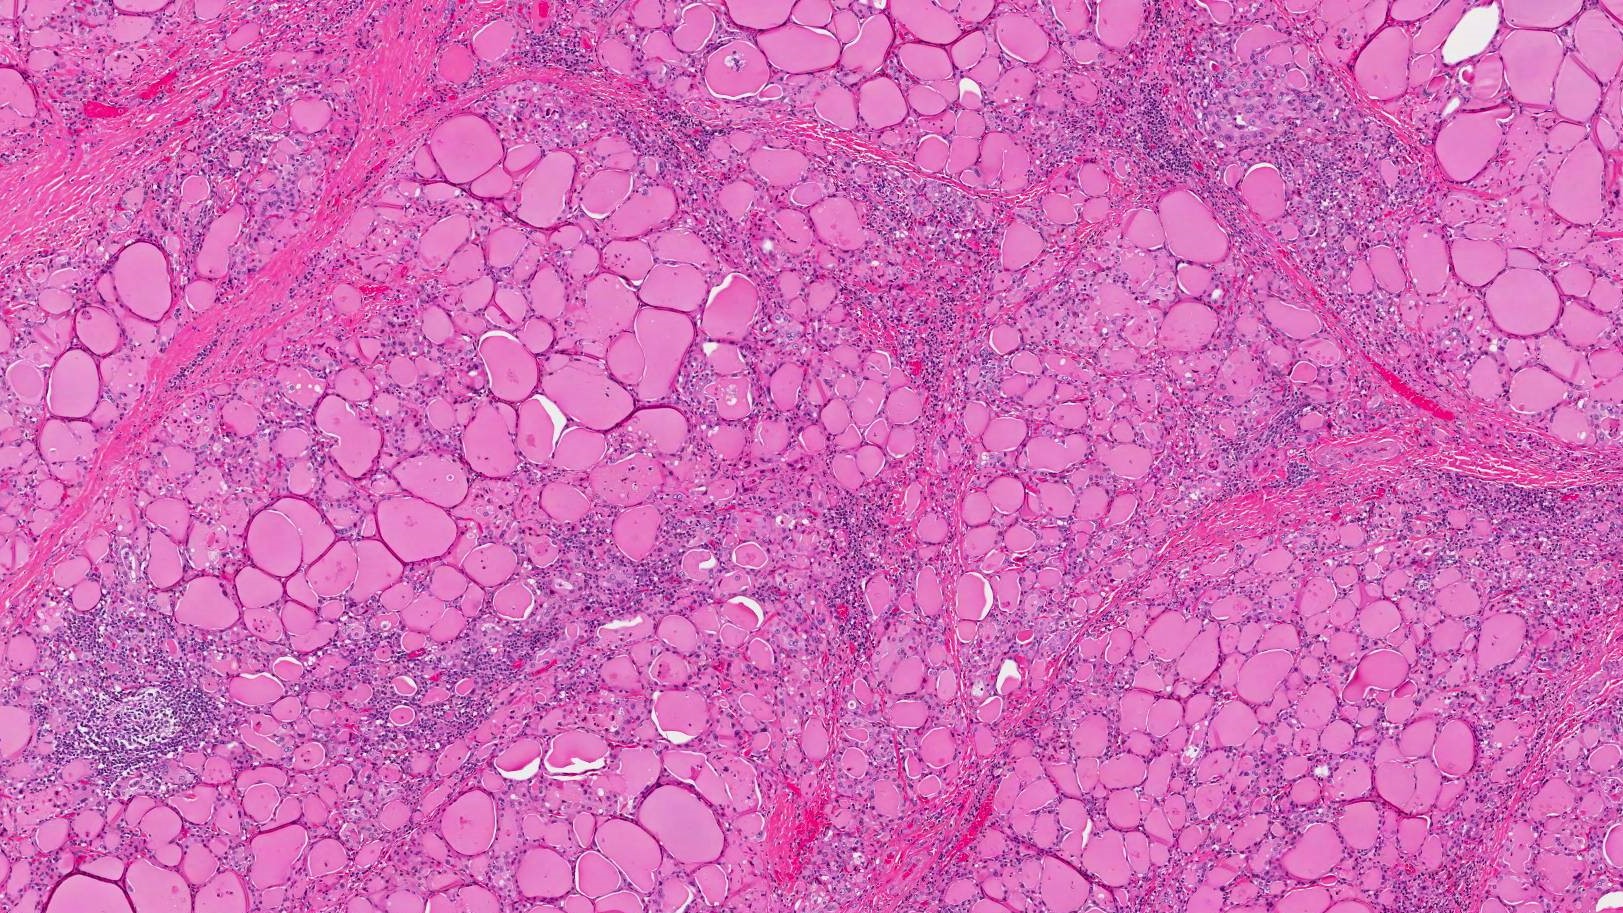

Nodular regenerative hyperplasia (NRH) is a rare liver disease, characterised by the growth of nodules within the liver, resulting in liver hyperplasia. While in many cases it is asymptomatic and thus goes undetected – or is only discovered incidentally while investigating some other medical condition – in some people it results in non-cirrhotic portal hypertension (NCPH). NCPH is generally less severe than the much more common portal hypertension due to cirrhosis. Complications of NCPH can include jaundice, ascites, splenomegaly, and bleeding esophageal varices. Most people with NRH retain normal liver function – even among the subset who go on to develop NCPH – and liver failure in NRH is uncommon. Only a small proportion of NRH patients will ever require liver transplantation.